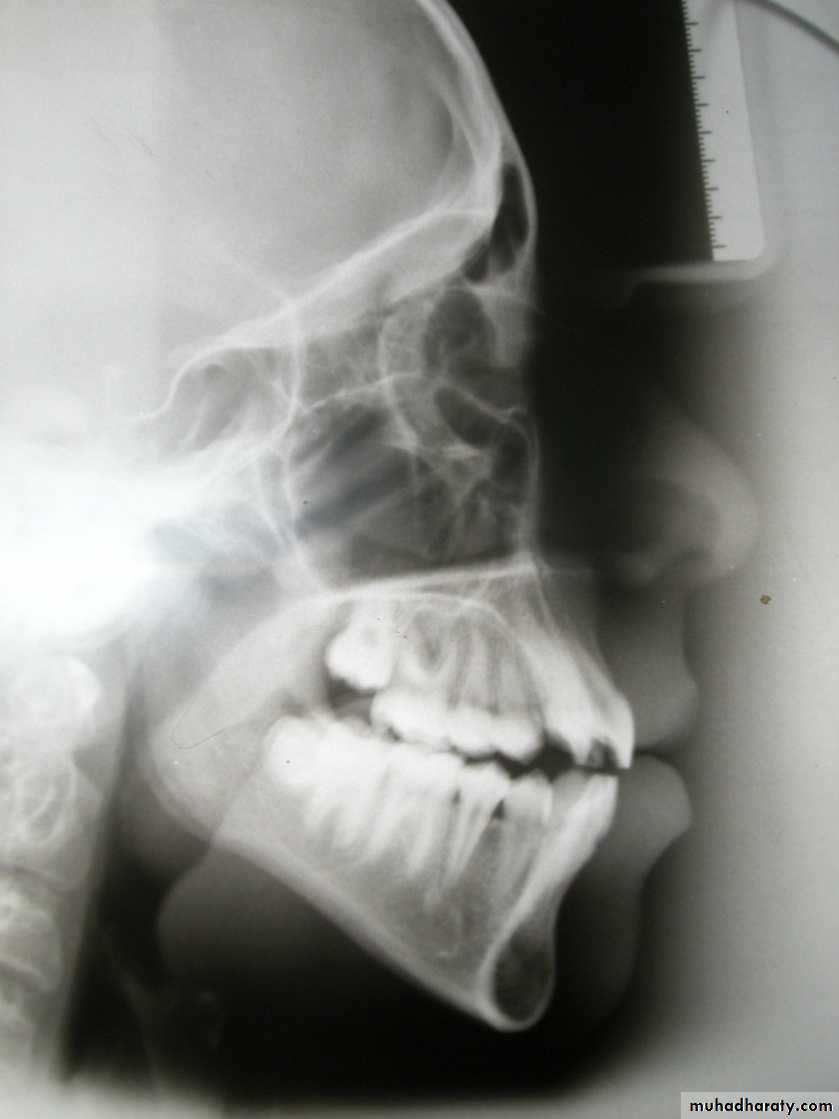

Antero-posterior skeletal relations

SNA angle (82 + 3)

Indicates antero-posterior position of maxillary apical base in relation to the cranial base: Large angle = Prognathic maxilla

Normal angle = Orthognathic maxilla Small angle = Retrognathic maxilla

SNB angle (79 + 3)

Indicates antero-posterior position of mandibular apical base in relation to the cranial base

Large angle = Prognathic mandible

Normal angle = Orthognathic mandible

Small angle = Retrognathic mandible

ANB angle (3 + 1)

Indicates the skeletal relationship between maxilla and mandible:

Large angle = postnormal relation (skeletal class II)

Normal angle = Normal relation

(skeletal class I)

Small angle (reverse) = Prenormal relation (skeletal calss III)

A-B / FOP angle (90 + 5):

Indicates the skeletal relationship between maxilla and mandible with reference to FOP :

Small angle = Prenormal relation

(skeletal calss III)

Skeletal AssessmentWits (AO-BO)

Facial angle

87° + 3

Indicate the anteropost

Position of the chin

N-S-Gn (Y-Axis) = 66⁰

This angle determine the position of the mandible relative to the cranial base

Vertical skeletal relations

MM angle (27 + 5)

Large angle = Skeletal open bite

Normal angle = Normal

Small angle = Skeletal deep bite

Frankfort-mandibular angle (27 + 5)

Dentoskeletal relations

UI / Mx plane angle (108 + 5)

LI / Mn plane angle (90 + 3)

Interincisal angle (133 + 10)

LI / A-Pog distance (0 + 2 mm)